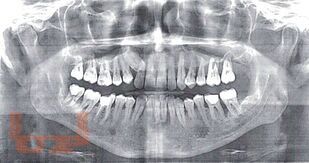

Эффективность трансдермальной системы гель «Поликатан» и «Тизоль» в комплексном лечении воспалительных заболеваний пародонта

В учебном пособии освещаются вопросы актуальности воспалительных заболеваний пародонта в стоматологии и социуме, аспекты этиологии и принципов лечения пародонтопатологий. Особое внимание уделяется применению геля «Поликатан» и «Тизоль» в комплексном лечении воспалительных заболеваний тканей пародонта.